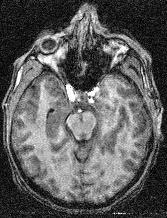

If the previous choices did not work, the problem may stem from some artifact hiding in some places the black areas corresponding to the skull:

In such cases, the initial binarization which is trying to fill small cavities resulting from noise has to be discarded, otherwise the skull is partly cancelled and the erosion has not a chance to do its job. Try the following variants:

"Standard/Robust... without regularisation"